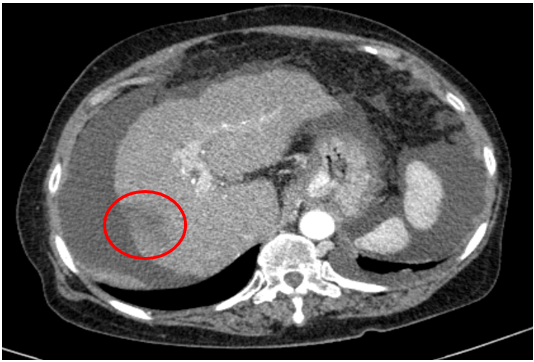

Tháng 11/2025

Chụp cắt lớp vi tính ổ bụng

Gan: biến đổi hình thái, bờ gan mấp mô không đều. Nhu mô gan có nhiều nốt giảm tỷ trọng trước tiêm, sau tiêm ngấm thuốc kém đường kính dưới 10mm dạng nốt xơ. Hạ phân thùy VII gan phải sát bao gan có nốt kích thước 22x31mm giảm tỷ trọng trước tiêm, sau tiêm không ngấm thuốc

Dịch tự do ổ bụng

=>U gan đã giảm kích thước, không còn tăng sinh mạch (Vòng tròn đỏ)